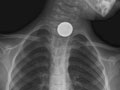

• Find foreign objects, such as coins or other small pieces of metal, in the tube to the stomach (esophagus), the airway, or the lungs. A chest X-ray may not be able to see food, nuts, or wood fibres.

A foreign object is seen in the esophagus, breathing tubes, or lungs.